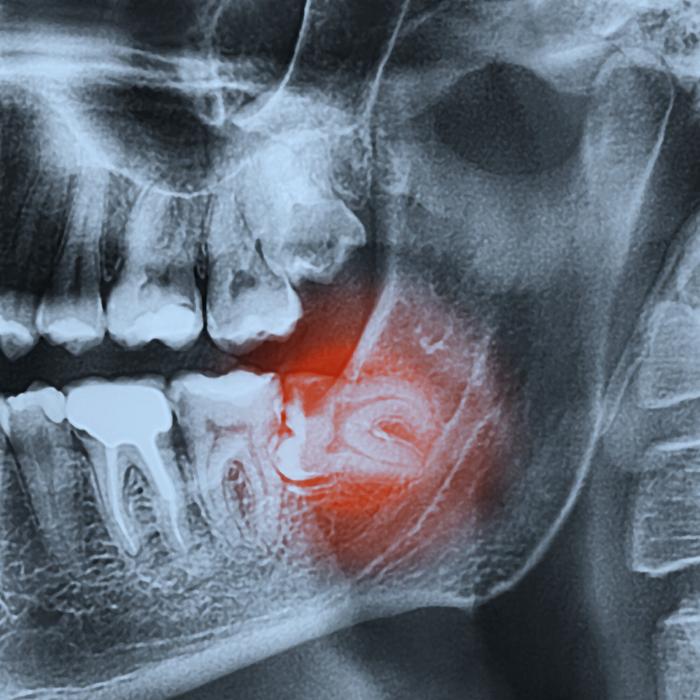

When a tooth is severely damaged or impacted, extraction may be necessary. We numb the area, gently loosen the tooth, and remove it. For wisdom teeth, we assess their position and may recommend removal to prevent crowding or infection. Post-operative care instructions are provided to ensure proper healing.